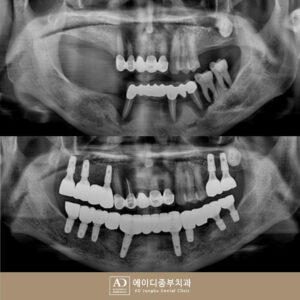

양산전체임플란트, 녹아내린 잇몸뼈로 흔들리는 치아 발치 후 다수 임플란트 식립

양산전체임플란트, 녹아내린 잇몸뼈로 흔들리는 치아 발치 후 다수 임플란트 식립 치아에도 각각의 역할이 있다는 거 알고 계셨나요? ​ 그중에서도 어금니는 음식을 잘게 부수어 소화시키는 저작기능에 90% 이상 관여하고 있지만 구강 내 안쪽에 위치해 있어 관리에 소홀해지는 경우가 많아 충치나 각종 치주 질환에 노출되기 쉬운데요. ​ 이러한 이유로 인해 어금니가 손상되거나 더보기…